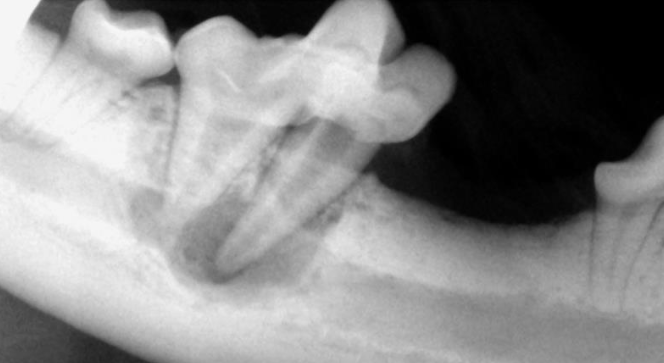

16

Q

DX?

A

LX périapicale et fistule